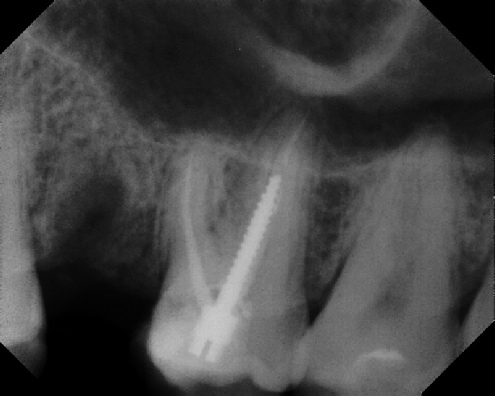

Root Canal Retreatment - Meriden 8 mos. recall Post-op Pre-op